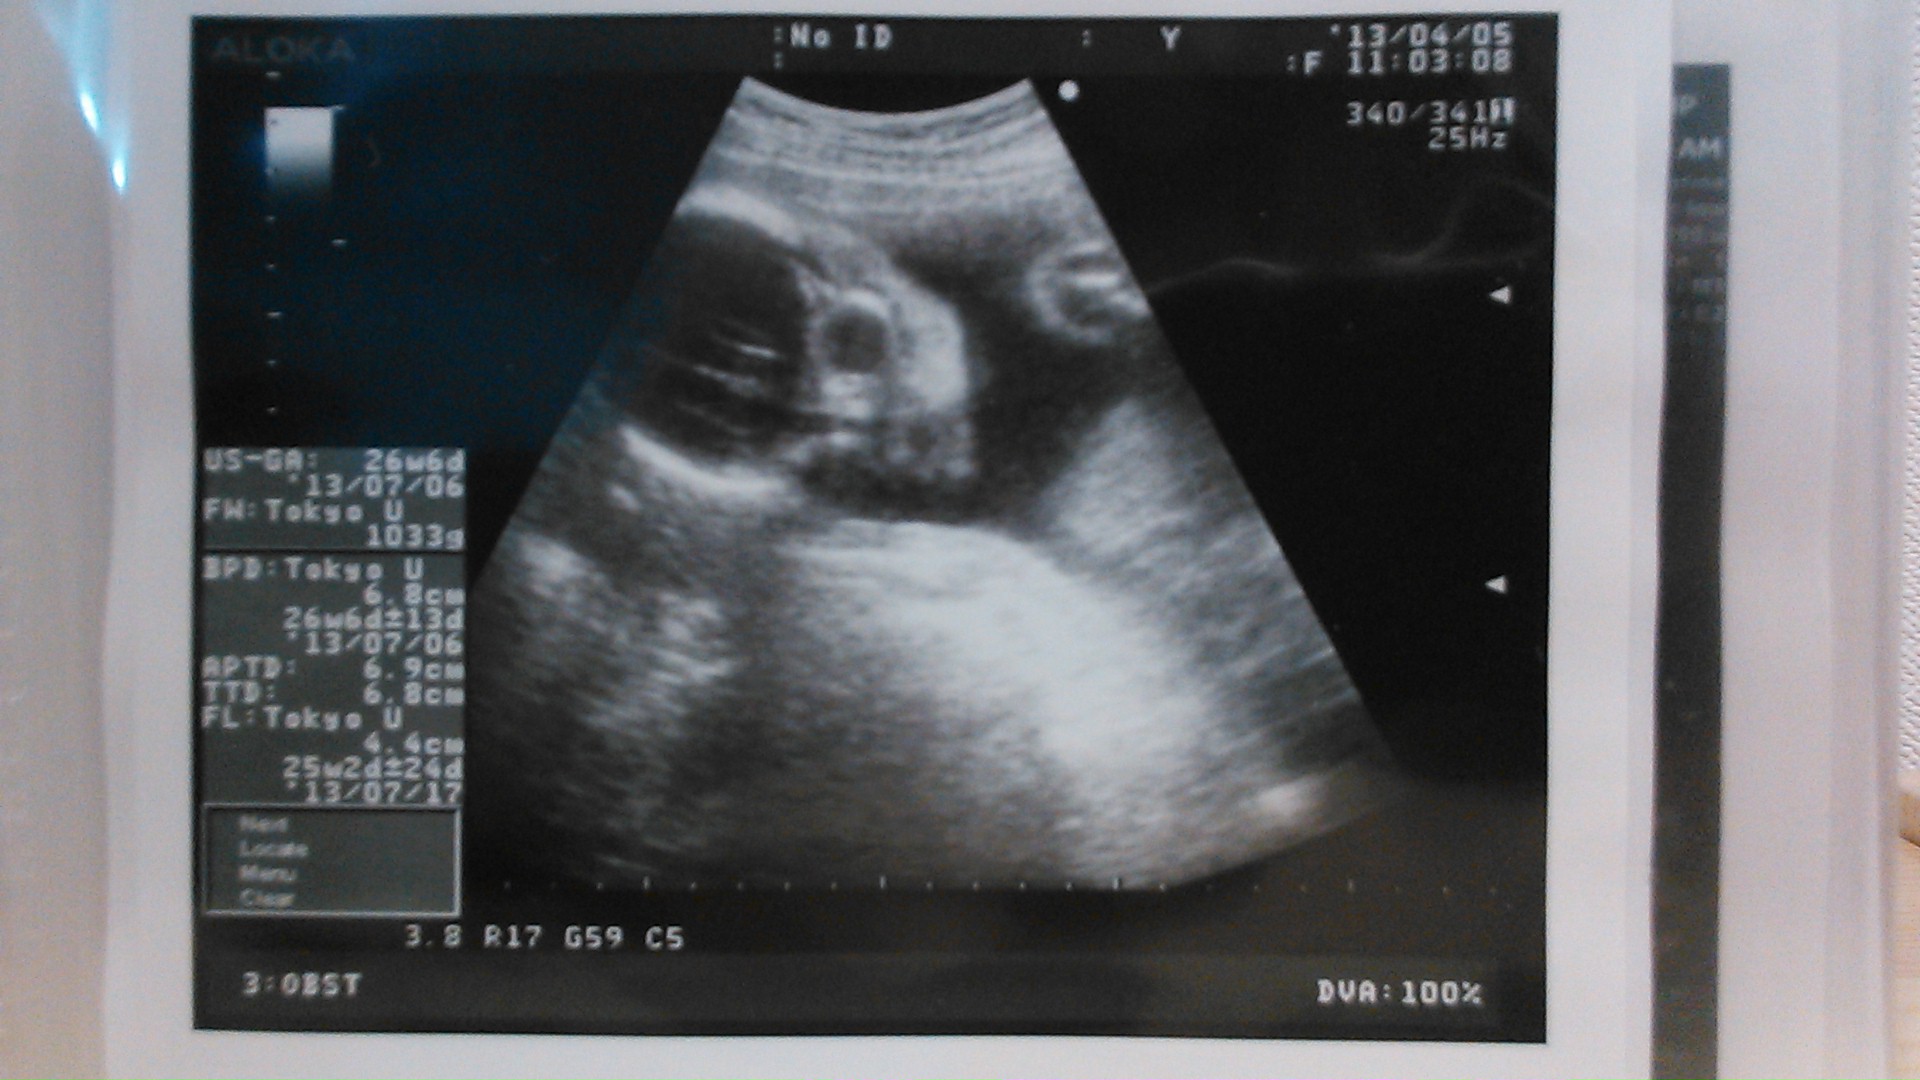

echo